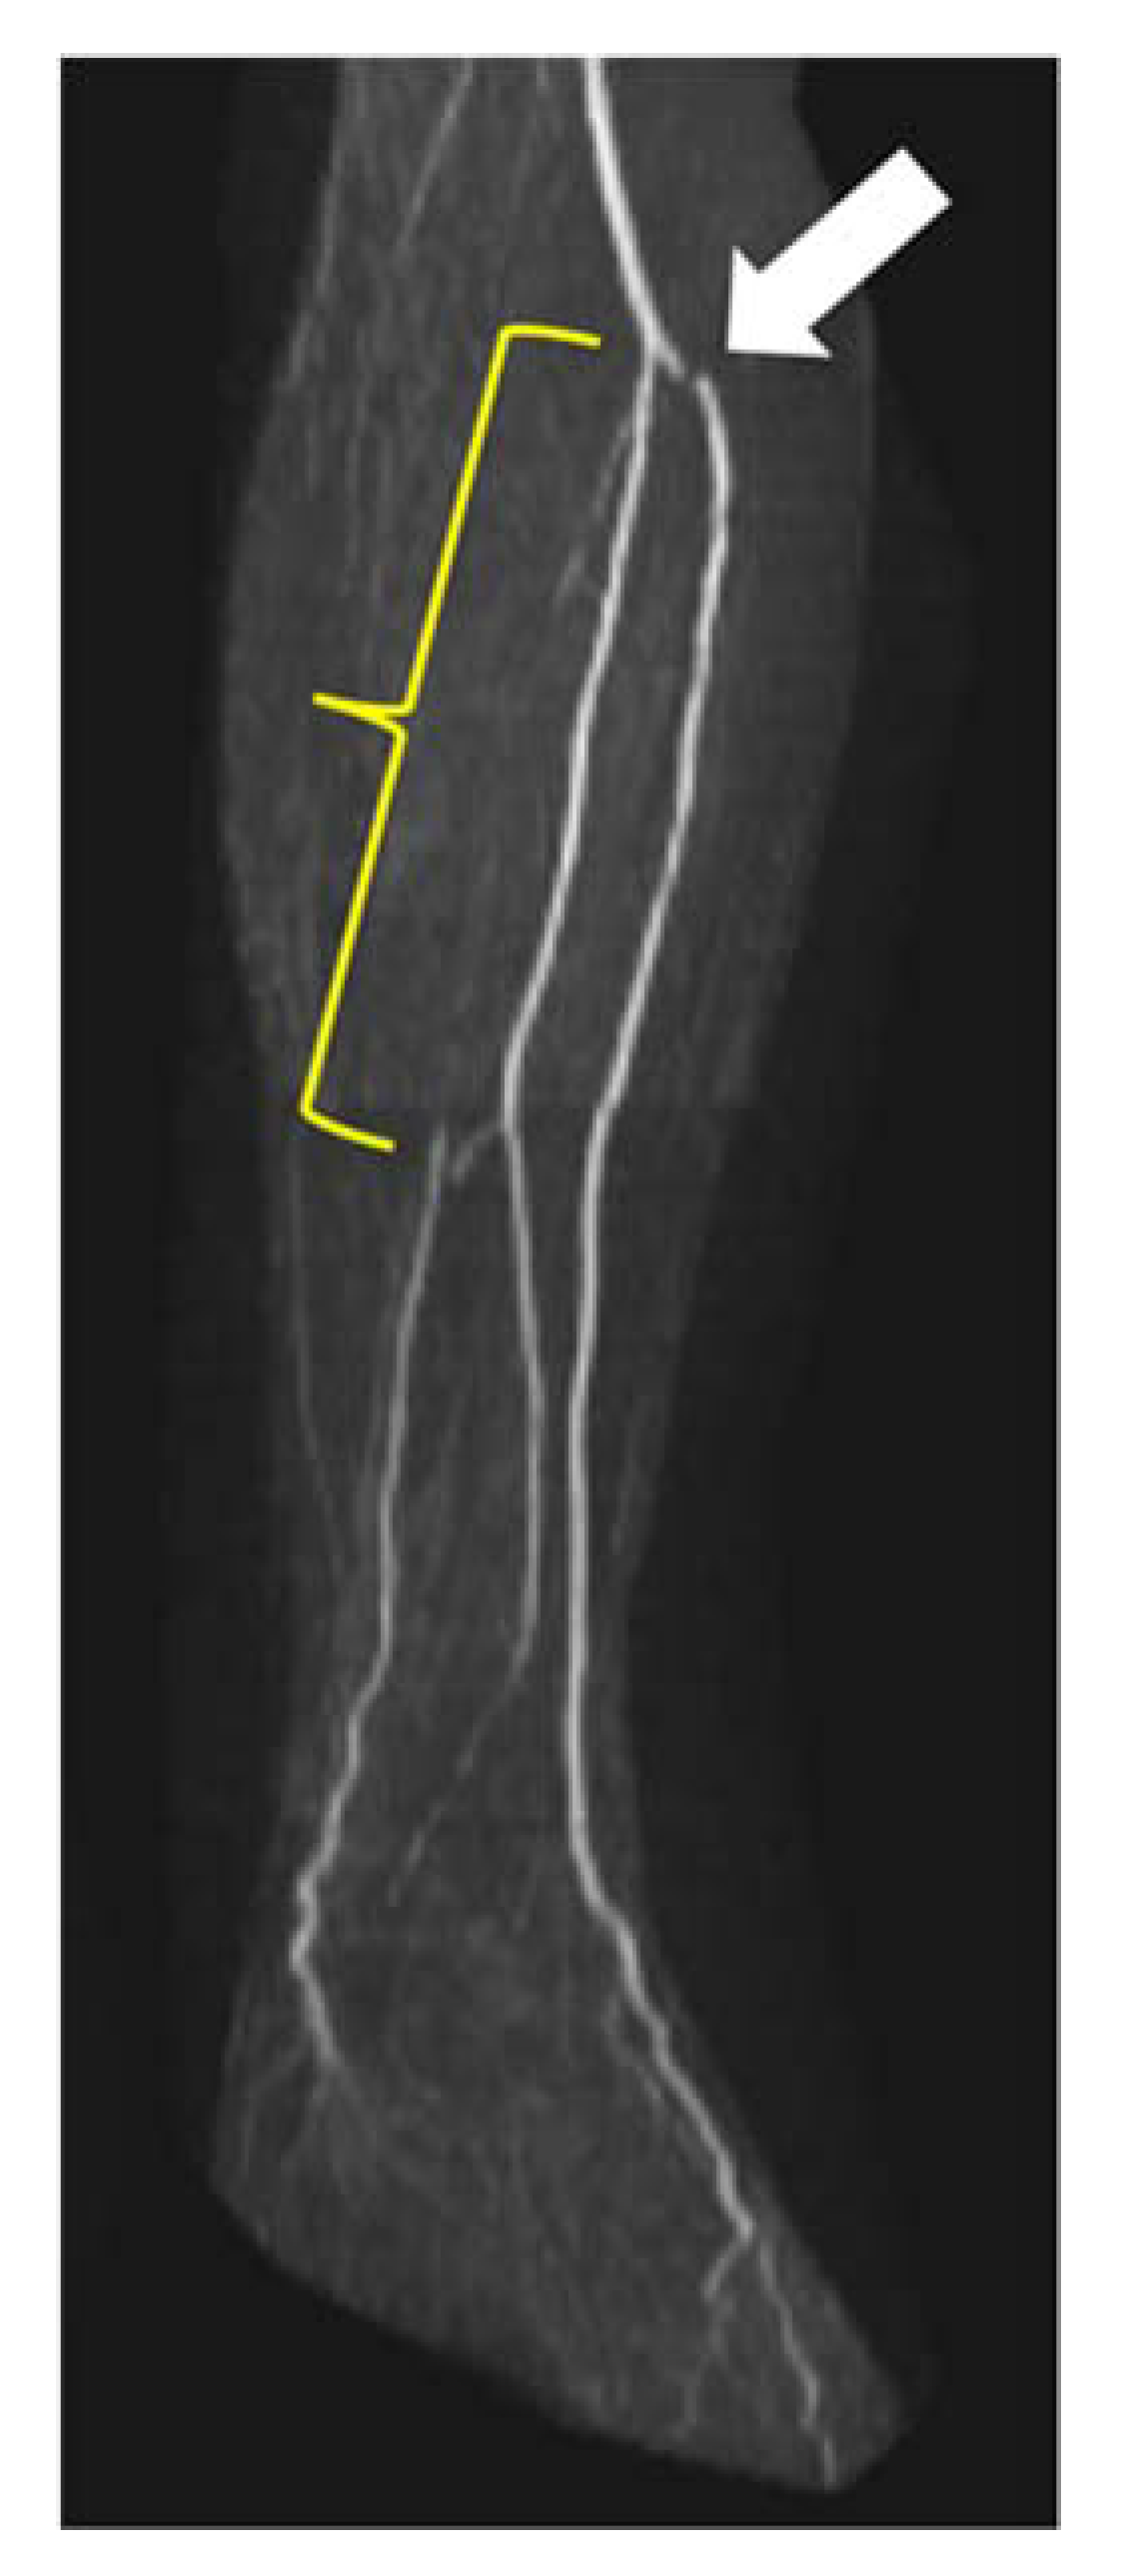

The AT was stenosed in 0.5% (1/200) of cases and the PT in 1.0% (2/200) of cases along the entire vessel length. Combined stenoses in the proximal and middle thirds of PT were found in 1.0% (2/200) of cases. Overall, stenoses could not be evaluated in 5.5% (11/200) of vessels. Figure 6 shows an example of a long-distance stenosis of the posterior tibial artery.

Figure 6.

Stenosis in lower leg arteries visualized by QISS-MRA. Long-distance occlusion of the left PT (yellow curved bracket). Note the distal PT, which is refilled by the FA. Harvesting of the fibular artery is prohibited in this case because it is now the main supply to the foot. The white arrow points to a stair-step artifact.